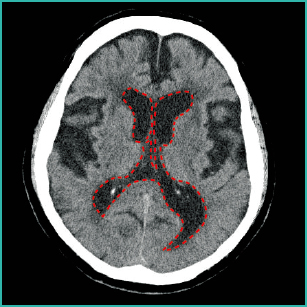

1)くも膜下出血と水頭症(急性水頭症)

図2において、脳室は拡大し、側脳室とくも膜下腔に血液を示す高吸収域(=白い)を認めており、急性水頭症を起こしています。

本症例は椎骨動脈の解離性動脈瘤破裂によるくも膜下出血発症直後の状態です(Hunt&Hess分類のGradeⅡ、くも膜下出血の画像の見方とケアでの活用ポイント参照)。

くも膜下出血によりくも膜下腔に流出した血液は、脳溝に血液が貯留し、さらにくも膜下腔から側脳室へと血液が流れ、側脳室に血液が貯留していることがわかります。

くも膜下腔に貯留した血液が髄液を吸収する部位に付着することで生じる吸収障害を認め、急性水頭症を合併しています。

急性水頭症は、くも膜下出血のみでなく脳室内穿破を伴う脳出血でも生じる可能性があります。また、出血による水頭症は吸収障害による交通性水頭症のほかに、血液が脳室の出入口で固まることで循環障害を認め、非交通性水頭症を起こすこともあります。